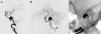

MethodsA total of six patients were treated: four patients with five aneurysms, one patient with an MCA stroke, and one patient with a meningioma requiring preoperative embolization were initially thought not to be amenable to endovascular treatment. The decision was made to treat these patients with transcirculation approaches. All patients were treated by one interventionist. One aneurysm was located in the cavernous internal carotid artery (ICA), one in the vertebral artery, two in the paraclinoid ICA, and one in a cerebellar AVM feeder vessel were treated.

ResultsFive of six patients (83%) made a full neurologic recovery. Three aneurysms were treated to complete occlusion, one aneurysm was left with small residual neck filling, and one aneurysm was not able to be treated. One patient underwent mechanical thrombectomy of a middle cerebral artery (MCA) embolus and MCA filling was restored after treatment. One patient underwent complete embolization of the deep vascular supply of a meningioma.